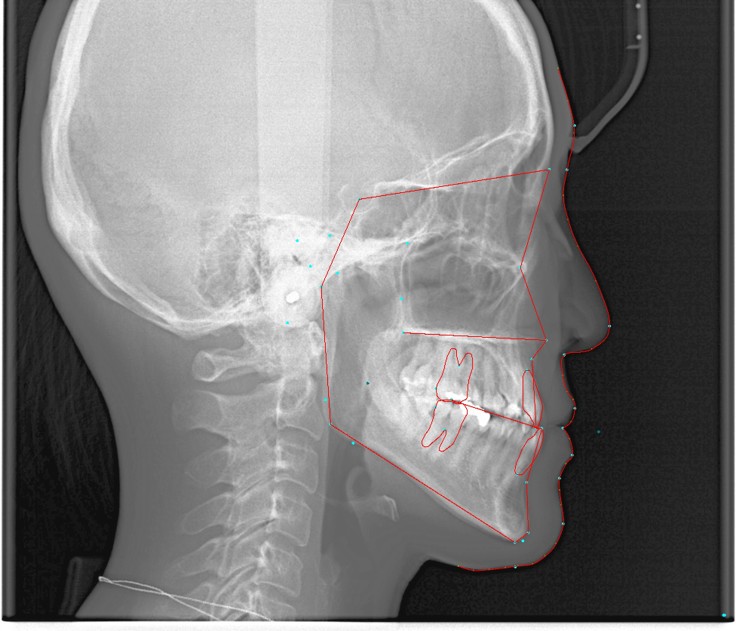

□ セファロ分析

セファロ分析

検査結果、写真などの資料をご覧いただきながら、現在の症状と問題点についてと作成したオーダーメイド治療計画のご説明をいたします。